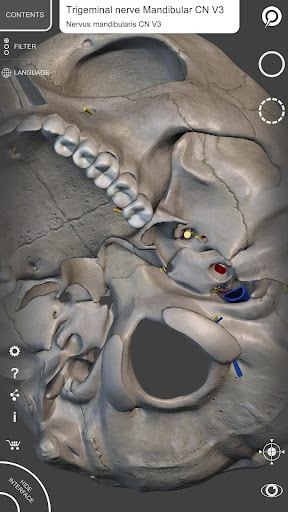

Mỗi xương của bộ xương người đã được tái tạo ở dạng 3D, bạn có thể xoay và phóng to từng mô hình và quan sát chi tiết từ mọi góc độ.

Bằng cách chọn mô hình hoặc ghim, bạn sẽ được hiển thị các thuật ngữ liên quan đến bất kỳ bộ phận giải phẫu cụ thể nào, bạn có thể chọn từ 12 ngôn ngữ và hiển thị các thuật ngữ bằng hai ngôn ngữ cùng lúc.

• Bề mặt của bộ xương có kết cấu độ phân giải cao lên đến 4K

• Xoay và Phóng to mọi mô hình trong không gian 3D

• Ghim tương tác cho phép trực quan hóa thuật ngữ liên quan đến mọi chi tiết giải phẫu

• Các thuật ngữ giải phẫu và giao diện người dùng có sẵn bằng 12 ngôn ngữ: tiếng Latinh, tiếng Anh, tiếng Pháp, tiếng Đức, tiếng Ý, tiếng Bồ Đào Nha, tiếng Nga, tiếng Tây Ban Nha, tiếng Trung, tiếng Nhật, tiếng Hàn và tiếng Thổ Nhĩ Kỳ

• Các thuật ngữ giải phẫu có thể được hiển thị bằng hai ngôn ngữ cùng một lúc